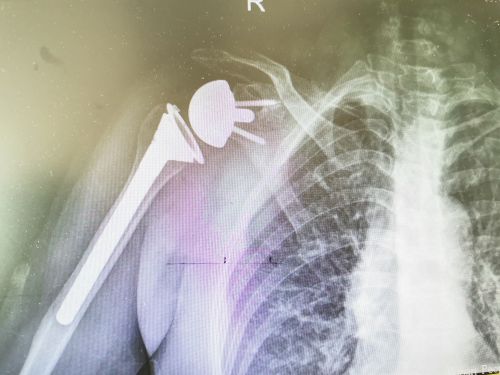

反肩关节置换术后影像。

入院后完善了核磁共振等检查,结果显示:右肩袖损伤(冈上肌腱、冈下肌腱全层撕裂伴回缩)。“对于这种巨大的、不可修复的肩袖撕裂,普通的修补手术效果不好,只能进行反肩关节置换”,王靖主任医师带领团队经过认真仔细的分析讨论,为患者制定精准的手术方案后,于2019年5月26日在全麻下为余女士施行右侧反肩关节置换手术。通过这种省内首次开展的新术式,让患者肩关节旋转中心下移,术后,患者可以利用三角肌的力量完成肩袖外展的功能,恢复正常的关节活动度。